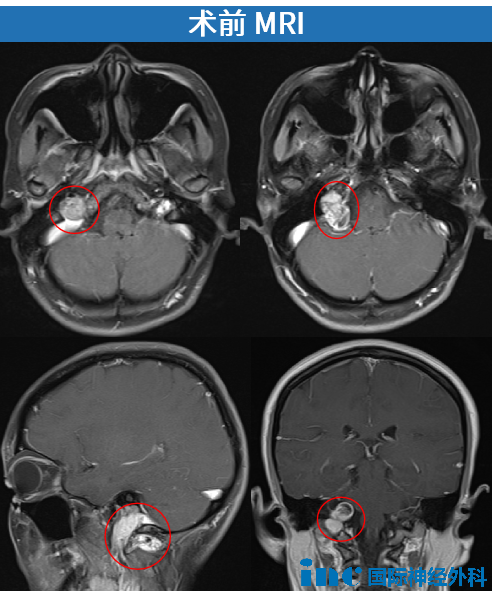

43岁的秦女士,其颈静脉孔区潜藏着一个“哑铃型”肿瘤,最大截面尺寸约为40 * 13毫米。秦女士已出现舌肌萎缩、肩膀无力等临床症状。通过INC国际神经外科医生集团,他们最终联系到巴教授。

这是一台极具挑战性的手术。一个呈哑铃型的肿瘤占据了颈静脉孔区,其形态横跨颅内与颅外空间,肿瘤两端呈现膨大状态,紧密嵌顿于该解剖区域。舌咽神经的起始部已发生瘤化改变,与肿瘤组织紧密粘连、难以分离;而肿瘤向颅外生长的部分,则与后组颅神经相互纠缠,形成致密粘连。